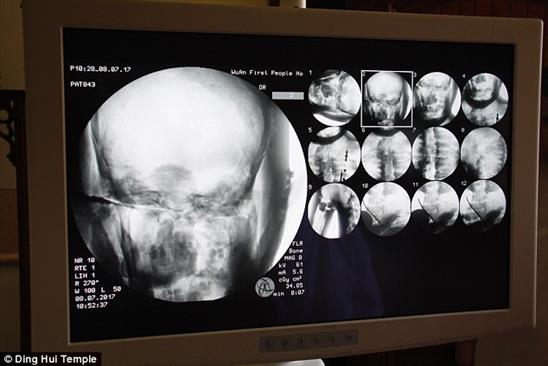

Xác ướp thiền sư Ci Xian được đem đi chụp cắt lớp.

Theo Daily Mail, thi hài thiền sư Ci Xian mới được đem đi chụp cắt lớp (CT) tại chùa Dinghui, ở Vũ Hán, phía bắc tỉnh Hà Bắc, Trung Quốc.

Thiền sư Ci Xian là nhà sư được tôn kính vì ông đã dày công đi từ Ấn Độ thời cổ đại sang Trung Quốc để truyền bá Phật giáo. Buổi chụp CT diễn ra ngày 8.7 trước sự chứng kiến của các nhà sư, cơ quan báo chí và các tín đồ.

Mọi người đều hết sức kinh ngạc khi thấy thi hài thiền sư Ci Xian vẫn còn nguyên vẹn bộ xương, và cả bộ não.

Bác sĩ Wu Yongqing nói sau khi chụp CT: “Chúng tôi kiểm tra phần xương của ông ấy và thấy vẫn khỏe mạnh như người bình thường. Hàm trên, răng trên, xương sườn và các khớp vẫn hoàn chỉnh. Điều này thật đáng kinh ngạc”.

Kết quả cho thấy xác ướp còn nguyên vẹn như người sống.